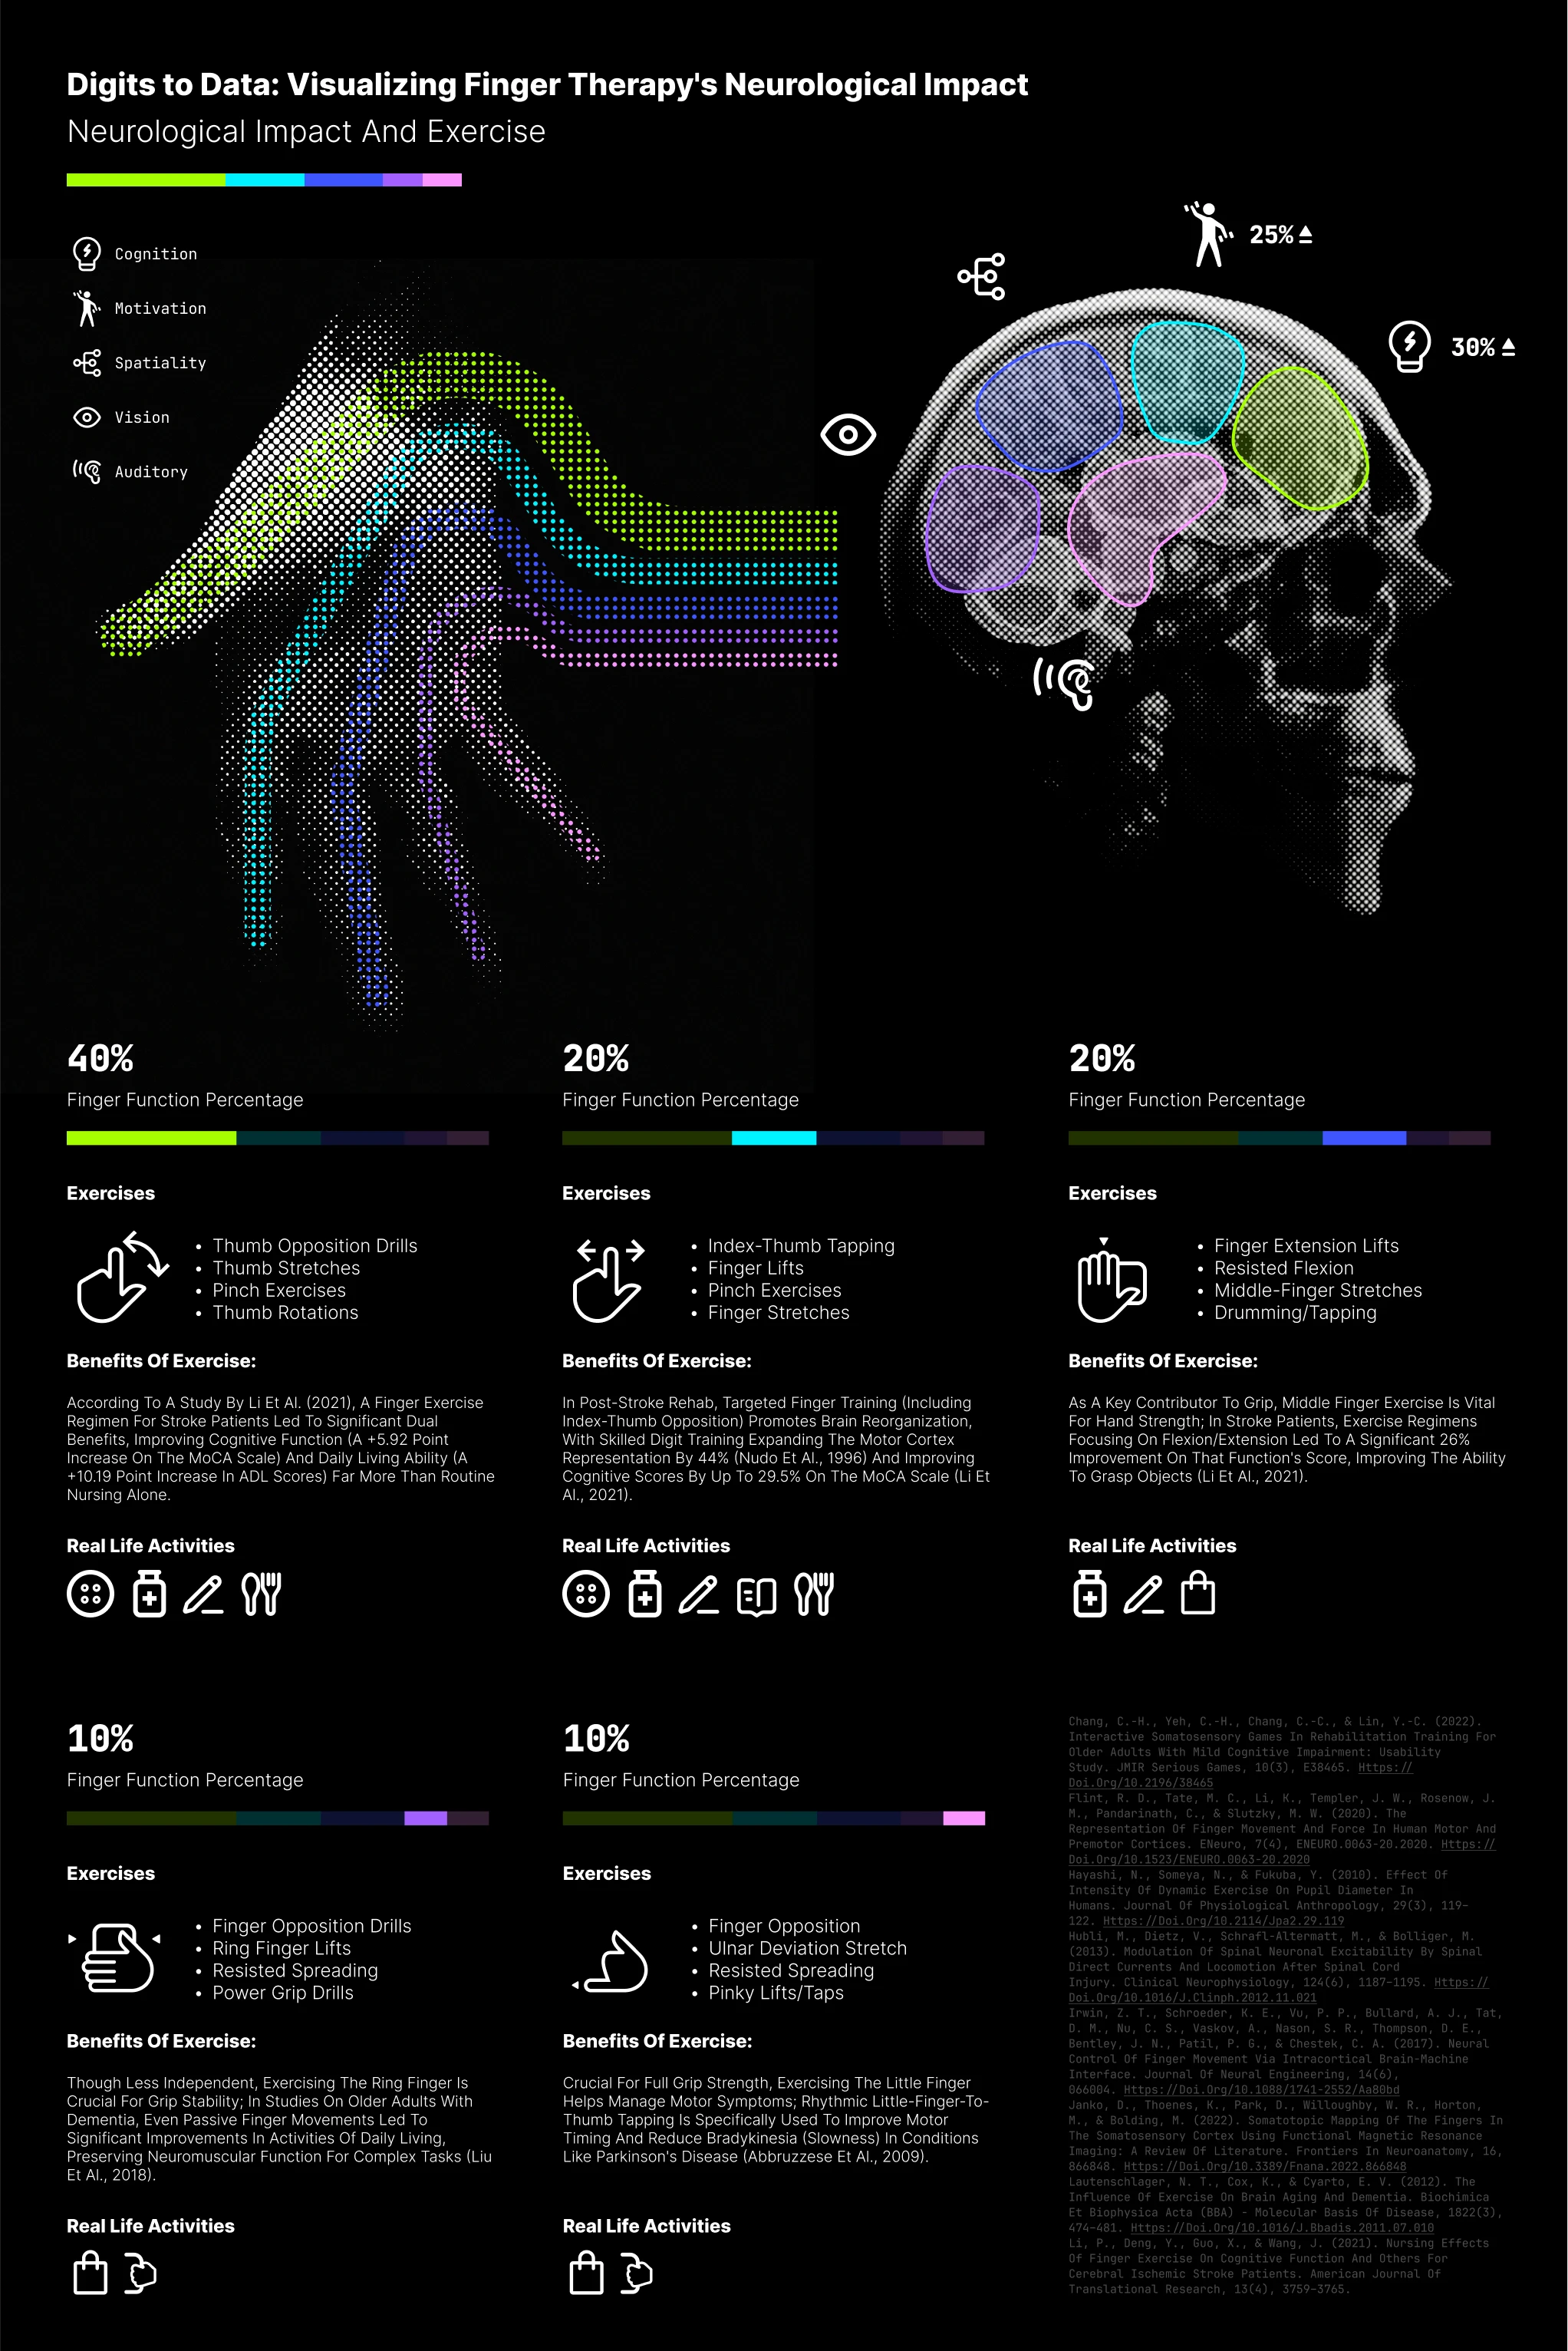

Visualizing Finger Therapy's Neurological Impact

A data visualization illustrating the impact of finger therapyon the nervous system.

Introduction to thesis research: "Human-Centered Design for Maintaining Senior Hand Grip Strength." This visualization conveys design concepts and research direction by clearly illustrating the profound impact of finger therapy on the nervous system.